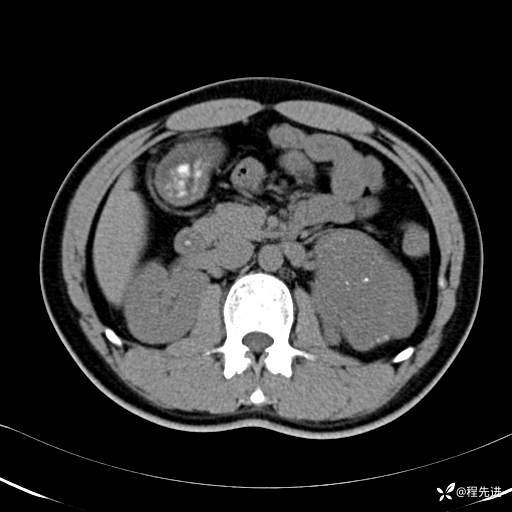

【腹盆】特别精彩病例|体检发现的左侧腹膜后占位期待您的精彩解读

患者年龄:25岁

简要病史:体检发现

CT平扫:(CT值:平扫,27HU,动脉期,27HU,门静脉期,31HU,平衡期,32HU)

冠状位重建: